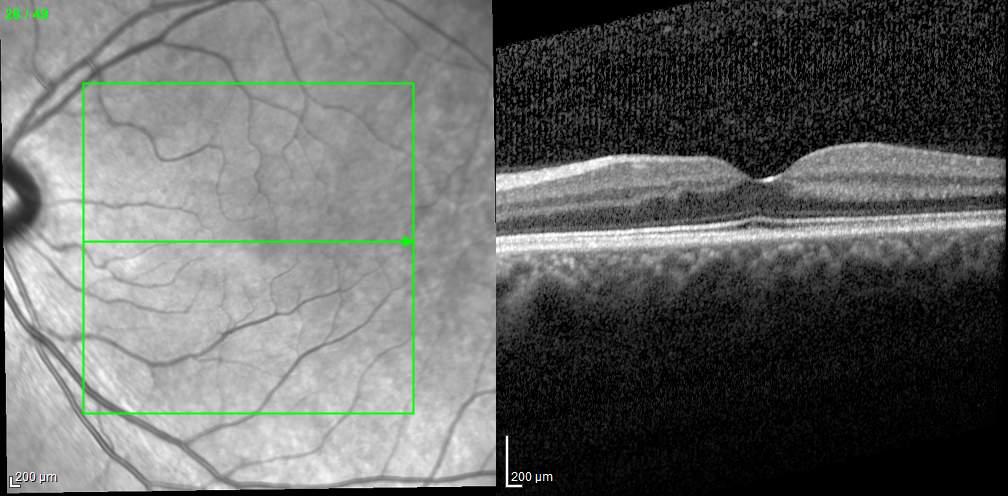

MNV may also develop in patients with central serous chorioretinopathy. In this condition, the pathogenesis of MNV is not yet fully understood. It is known that it can occur after laser photocoagulation or photodynamic therapy as a compensatory response to treatment; however, MNV may also develop in cases without history of laser treatment. In these cases, MNV may develop in a manner similar to AMD, where the rupture of Bruch’s membrane due to chronic RPE changes and long-standing serous pigment epithelium detachment allows for the growth of Type 1 neovascularization.33–36 (Figure 6)

Figure 6. Multimodal imaging of Type 1 macular neovascularization secondary to central serous chorioretinopathy. Fluorescein angiography (A and B) showing pinpoints of hyperfluorescence with leakage in the late phase. Indocyanine green angiography (C and D) displaying the central hyperfluorescent area and the adiacent area of choridal hyperpermeability. Fundus autofluorescence (E) revealing abnormalities of retinal pigment epithelium. The en face of optical coherence tomography angiography (F) showing the neovascular network and the B-scan displaying the shallow irregular retinal pigment epithelium elevation with subretinal fluid (G).